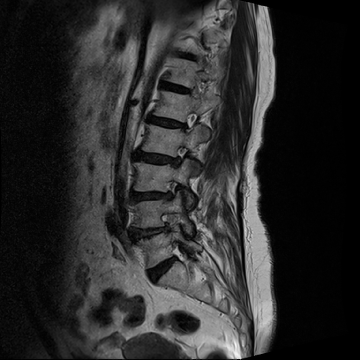

요추 협착증 수술 전·후

2020.08.30

2022.09.06

ㆍ환자 동의를 받은 자료이며, 이미지 사진은 실물과 다를 수 있습니다.

ㆍ모든 자료는 새움병원 자료입니다.